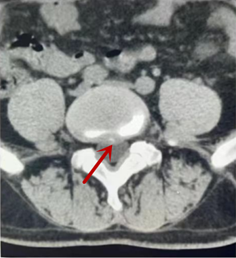

利器二:CT

CT利用X射線對(duì)人體檢查部位通過電腦切成若干層掃描,然后把每層的圖像都能顯示出來。CT相對(duì)于X光片具有更高的密度分辨力,可直接顯示X線片無法顯示的病變,觀察腰椎有無微小的骨折、骨質(zhì)有無破壞等骨質(zhì)情況、以及腰椎間盤突出、腰椎神經(jīng)根、椎管、椎間小關(guān)節(jié)的情況等。同時(shí)還可以通過后處理,重建腰椎矢狀位或冠狀位圖像,形成腰椎的3D圖像,更直觀地觀察病變部位,對(duì)腰椎手術(shù)風(fēng)險(xiǎn)具有提示作用,對(duì)手術(shù)方式的選擇具有指導(dǎo)意義,但是對(duì)神經(jīng)、脊髓損傷程度的顯示不如MRI,軟組織的分辨率仍有一定限制,對(duì)椎管內(nèi)病變顯示欠佳,且有一定的輻射。

箭頭提示椎間盤突出

從左向右依次為CT矢狀位重建圖像、三維重建圖像、軸位掃描圖像,箭頭提示腰1椎體爆裂性骨折